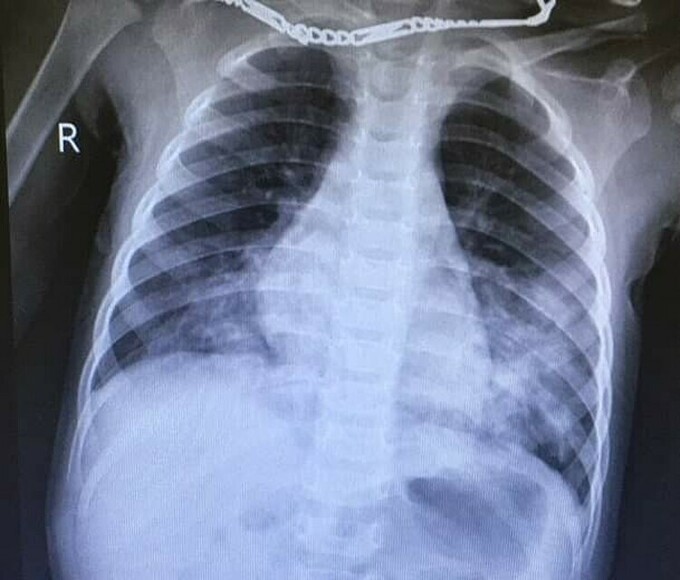

Nhập viện cấp cứu ngày 8/5, bệnh nhi được chẩn đoán viêm phổi, xuất huyết tiêu hóa nghi do ngộ độc chất tẩy.

Bác sĩ cho trẻ thở oxy, đặt sonde dạ dày, truyền dịch, tiêm kháng sinh, dùng thuốc giảm tiết axit. Hiện sức khỏe bé ổn định, đang được theo dõi sát tại viện Việt Nam - Thụy Điển Uông Bí